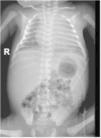

The patient was admitted to the intensive care unit, with subsequent detection of coagulopathy, cholestasis and persistent thrombocytopenia despite multiple transfusions. The results of cultures and serological tests were negative. The peripheral blood smear examination revealed the presence of vacuolated lymphocytes. The postnatal radiograph and ultrasound examinations detected hepatosplenomegaly (Fig. 3).